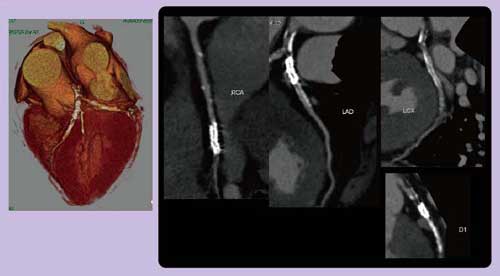

DEイメージングでは,100kVと140kVの画像を元に,ヨード成分を抜き出した“ヨード強調マップ(画像)”,および両者をフュージョンした“Composite Image(合成画像)120kV”の画像を作成することができる(図1)。これらの画像と,冠動脈CTやcoronary curved MPRなどを比較して読影する。DEイメージングによる心筋虚血評価のプロトコールは,ATP負荷は0.16mg/kg/minを3分間投与し,造影剤は4mL/sで100cc注入。通常の冠動脈CTより3〜5秒遅らせて撮影を行った。

図1 DEイメージングの解析原理

70歳,男性,3枝PCI後の症例で,再狭窄が疑われた。DEイメージングによる120kVの合成画像から作成した冠動脈CT(図2)では,多くの石灰化やステントがあるため再狭窄の有無は明らかではなかったが,ヨード強調マップ(画像)(図3)では心尖部側壁寄りや後位前壁に低灌流域が認められ,SPECTでも同一の場所で再分布を伴う虚血が認められた。このようにDEイメージングを用いることで,非常にクリアに虚血を描出できる可能性がある。

図2 Case 3:70歳,男性,3枝PCI後

DEイメージングの120kV画像から作成した冠動脈CT